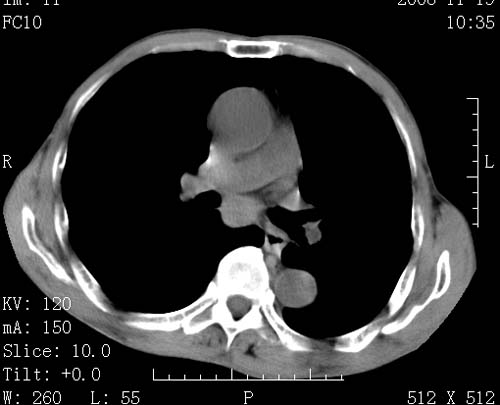

标题: CT16691:m 67 胃镜确诊食管下段及贲门癌 [打印本页]

标题: CT16691:m 67 胃镜确诊食管下段及贲门癌

术前查体,双肺部结节是转移?结核?请点评

首先考虑转移,纵隔内淋巴结亦肿大;

1)符合食管癌表现。2)两肺及纵隔淋巴结多发性转移瘤。3)左肺上叶舌段及两肺下叶炎症感染。

1)符合食管癌表现。2)两肺及纵隔淋巴结多发性转移瘤。3)左肺上叶舌段支气管扩张伴感染.

食管癌伴双肺转移,评述:肺部毛细血管网丰富,全身血液均快速流经肺部,癌细胞容易过滤定植,形成转移瘤,影象特点为以毛细血管末梢为中心的结节灶,边缘光滑锐利,少见有中心空洞着,不同来源的转移瘤可有各自特点,如甲状腺癌为双肺弥漫性微结节,本例有原发灶,双肺影象灶典型,左肺舌段条带状网格样伴胸膜天幕征,可视为癌性淋巴管炎。